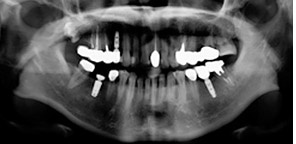

天津市中诺口腔医院(全国连锁·国家二级口腔专科医院)“立得用”种植体系对手术精准度要求更高,采用口腔CBCT技术诊断,从任意角度、任意方位,立体化观察牙槽骨情况,确定科学种植位置,设计出科学种植方案,立种、立用,生物相容性更好,更稳定牢固。

根据顾客牙槽骨密度、高度、宽度,在数字化辅助下自动避开血管和神经,以较短的时间和1微米的创口精度,精准快速种下每一颗种植体,当天做种植牙,当天就能戴牙。

为了保证种植牙的效果、质量,天津市中诺口腔医院(全国连锁·国家二级口腔专科医院)在种植牙之前会精准细致的检查顾客的口腔、牙齿状况,然后根据检查结果,综合分析种植牙顾客的身体状况,制定出种植牙的整体方案,让种植体和人体组织有效融合。

• 1拍片确诊

• 2确定方案

• 3三维重建